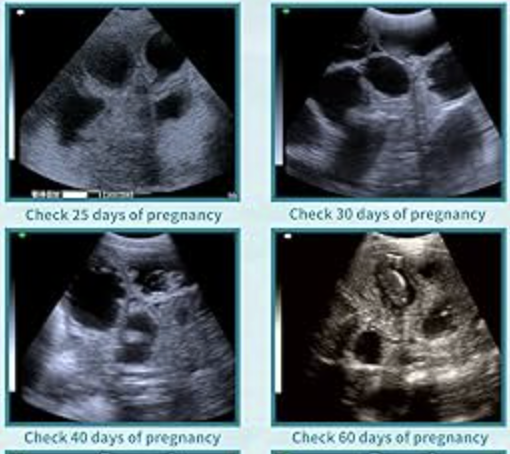

We are local breeders who own our own laptop ultrasound machine with a convex probe and offer pregnancy ultrasound confirmations for fellow breeders. Many ultrasound services charge $100+ for appointments. We offer the service for $50.

Ultrasound appointments are best scheduled between Day 28–35 post-breeding, which is the ideal window to confirm pregnancy in dogs.

This service is for pregnant vs. not pregnant confirmation. While we’re happy to make informal observations about possible litter size, ultrasounds are not reliable for counting puppies. Puppies can overlap or appear from different angles, so counts are never guaranteed.

Depending on how far along your dam is, it's sometimes possible to observe slight movements or early activity from the puppies, though this can vary by dog size, breed and litter. Seeing heartbeats on our machine is not guaranteed.

Please shave your dog’s belly prior to arrival to allow for the clearest imaging and a quicker scan. We can perform ultrasounds prior to 28 days, but we do not recommend coming too early for best viewing results. If you do not have a way to shave her, you can borrow our shaving & vacuum system for an additional $15, but you will need to shave her yourself.